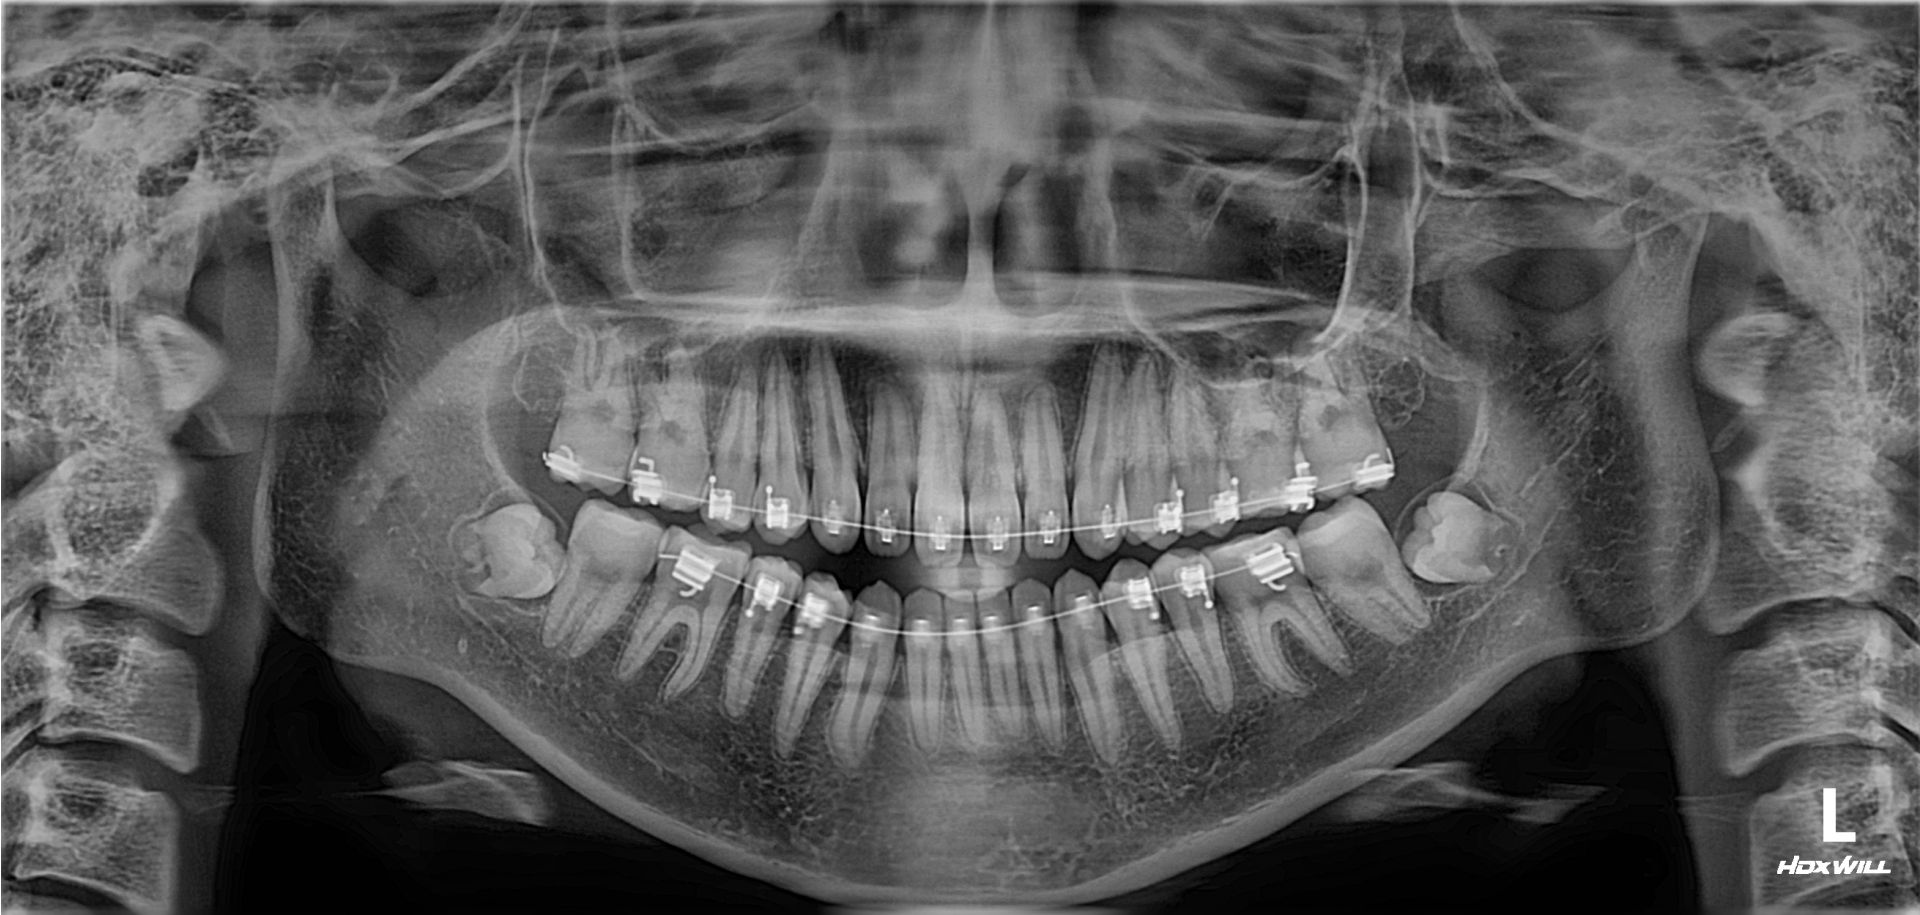

확장 개원 후, 첫 번째 사랑니 환자입니다. 잇몸 밖으로 보이지도 않고, 절개를 해도 뼈만 보이고 사랑니는 보이지를 않습니다. 이 정도면 사랑니 중에서도 난도가 높은 편입니다. 발치하는 데 얼마나 걸릴까요? 빨리 뽑는 것보다 잘 뽑는 게 중요하지만, 역설적으로 잘하는 의사는 빨리 뽑습니다. 그리고 약물 처방 외에도 주사 처방을 통해 붓기를 조절해 드립니다.

확장 개원 후, 첫 번째 사랑니 환자입니다. 잇몸 밖으로 보이지도 않고, 절개를 해도 뼈만 보이고 사랑니는 보이지를 않습니다.

이 정도면 사랑니 중에서도 난도가 높은 편입니다. 발치하는 데 얼마나 걸릴까요?